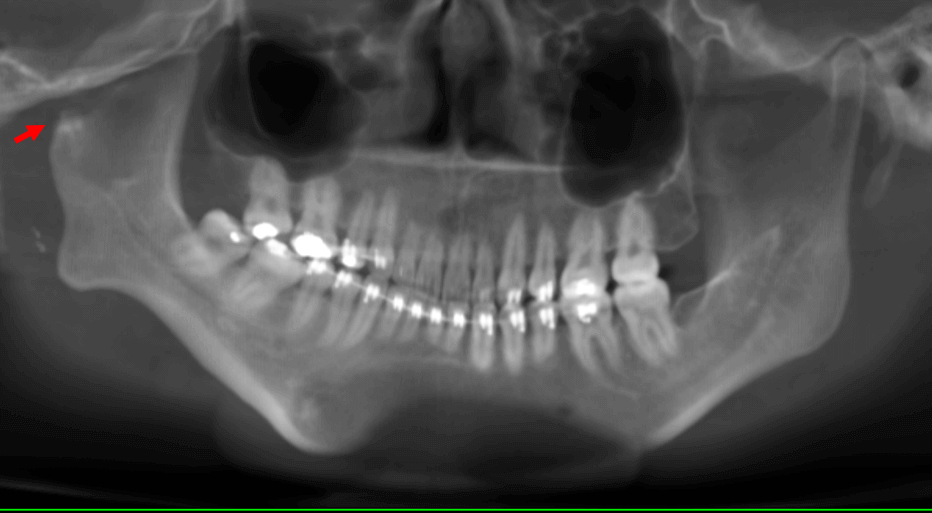

Fig.2

En cortes sagitales (Fig.2) se observa una leve proyección ósea compatible con un aparente cóndilo mandibular (flecha roja) lo que sugiere la hipoplasia del mismo, y la ausencia de la cavidad glenoidea y de la eminencia articular. Así mismo, se observa el elongamiento marcado de la apófisis coronoides (flecha amarilla).

Fig.4

En cortes coronales (Fig.4) se observa comparativamente ambas ramas mandibulares donde observa la adaptación ósea de la mencionada proyección ósea que funge como el cóndilo mandibular derecho (flecha roja). De forma contralateral, se observa la rama mandibular del lado izquierdo.